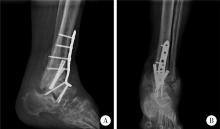

Figure 5

Postoperative radiograph of the left ankle after multi-joint arthrodesis A, lateral view; B, anteroposterior view."